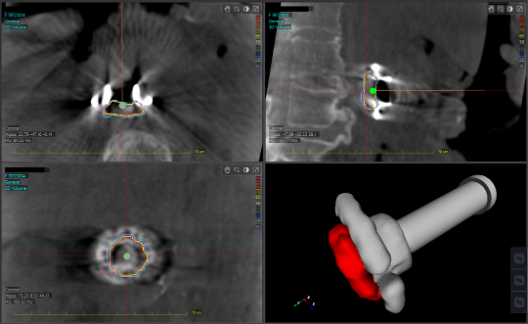

天津醫(yī)科大學(xué)腫瘤醫(yī)院近日完成的手術(shù),在全球首先實現(xiàn)了移動式CT圖像引導(dǎo)的胰腺癌術(shù)中精準(zhǔn)放療。由于患者腫瘤位置靠近重要血管,治療團(tuán)隊在術(shù)中將腫瘤完整切除后,利用醫(yī)療移動式C臂CT系統(tǒng)Cios Spin術(shù)中影像輔助實施放療手術(shù)方案:

利用先進(jìn)的術(shù)中CT設(shè)備以及獨有的去金屬偽影技術(shù),在30秒內(nèi)快速準(zhǔn)確地采集患者術(shù)中瘤床區(qū)域高質(zhì)量圖像

基于術(shù)中實時CT,對瘤床和復(fù)發(fā)風(fēng)險較高區(qū)域快速勾畫,計算并得到三維圖像和劑量分布

根據(jù)實時圖像進(jìn)行準(zhǔn)確、快速的劑量疊加

術(shù)中放療施用器根據(jù)治療計劃和患者術(shù)中圖像進(jìn)行準(zhǔn)確配準(zhǔn)